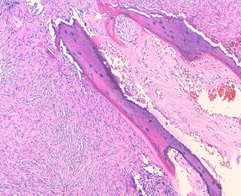

The histological examination revealed high cellular proliferation made of bundles and storiform structures. Tumor cells were fusiform with moderate cytonuclear atypia. There were 6mitosis /10high power fields. Hemangiopericytoma-like (figure 5) vessels were noted. This proliferation infiltrates the bone tissue and came in contact with the cerebral parenchyma. An immunohistochemical study was carried out: the tumor cells express the anti CD34 antibody, the anti bcl2 antibody, and a clear expression of STAT6. The proliferation index evaluated by the Ki67 is estimated at 20%. The diagnosis of the malignant solitary fibrous tumor was retained (high cell density, the cytonuclear atypia, and the high mitotic activity). The patient received postoperative radiotherapy. The patient progressed well postoperatively, in particular no fever or signs of intracranial hypertension, with satisfactory radiological control (Figure 6): the presence of minimal pneumocephalus with the completely unobstructed nasal cavity, without recurrence or metastasis, with a follow-up of 36 months.